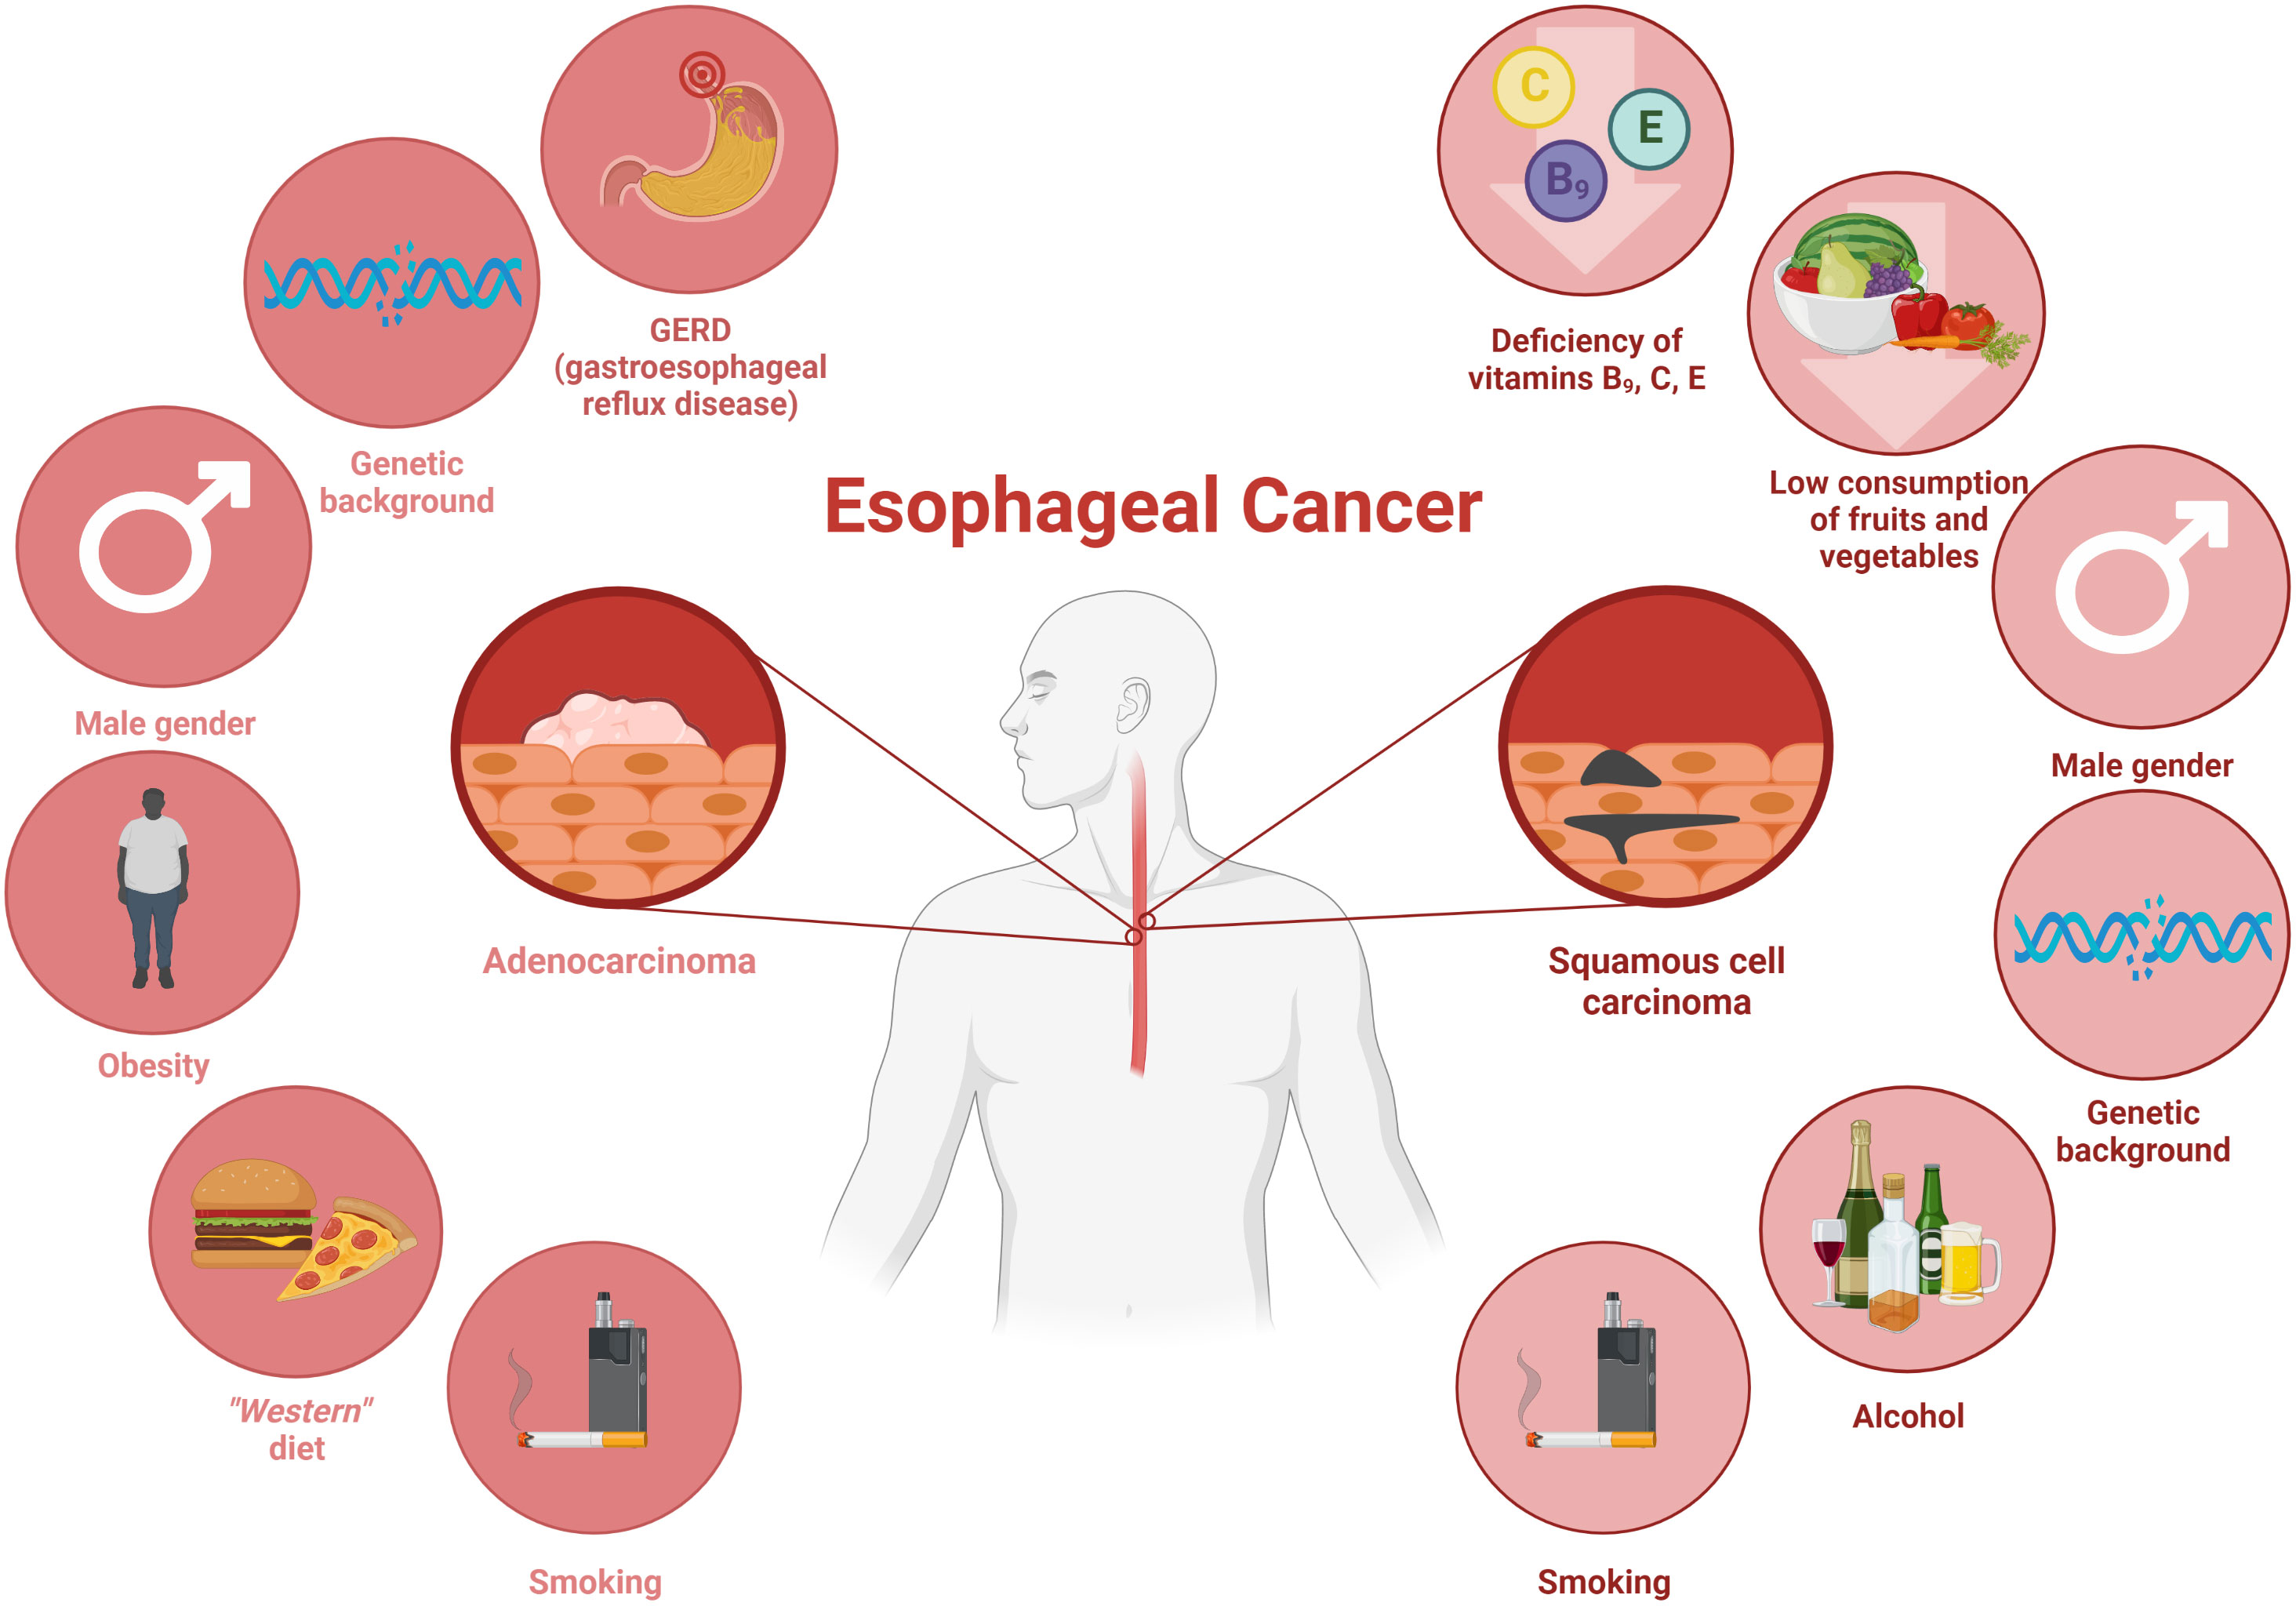

Esophageal Cancer Age Range Screening And Survival Rates